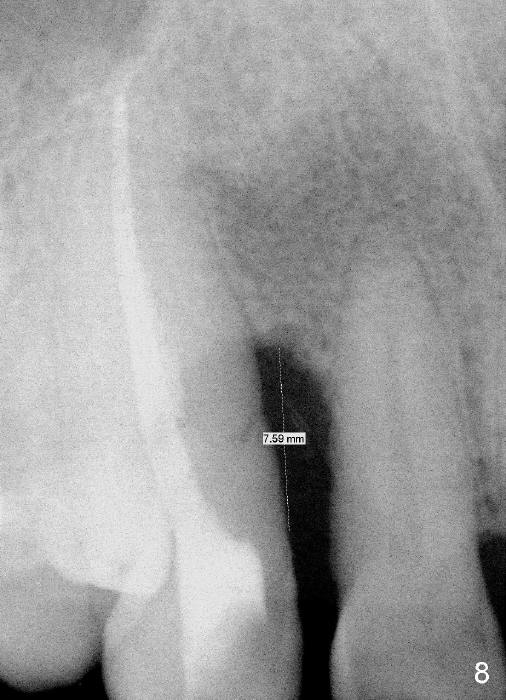

A male patient had trauma to the tooth #6 at the age of 13.  The affected tooth has remained asymptomatic for more than 30 years (Fig.1).   X-ray reveals an oblique root fracture (Fig.2 >) with radiolucency in the mesial alveolus (*, apparently normal trabecular pattern).  Six years later (Feb. 2011), an acute infection develops (Fig.4 *).  It requires incision & draining and antibiotic.  At that time, the trabecular pattern disappears around the fracture line mesially (Fig.3 *).  Four months later cone beam CT shows bone loss between #6 and 7 (Fig.5 *).  Root canal therapy is done as a palliative measure (Fig.6 R; C: Cavit).  Three months later, MTA (mineral trioxide aggregate) is placed in the coronal canal next to the fracture line (Fig.7 M).  It is hoped that MTA can promote nearby bone and cementum to regenerate to seal the fracture line.  Four months after MTA application, there is no sign of bone regeneration (Fig.8).  Bone is lost for approximately 7 mm.

The tooth is discolored probably due to the side-effect of MTA(Fig.9; photo taken 9 months post-MTA).  The mesial gingiva recedes (*).  There is mild persistent pain with purulent discharge mesiobuccally (Fig.10 >).  The corresponding pocket remains 7-8 mm deep in spite of root canal therapy and MTA.